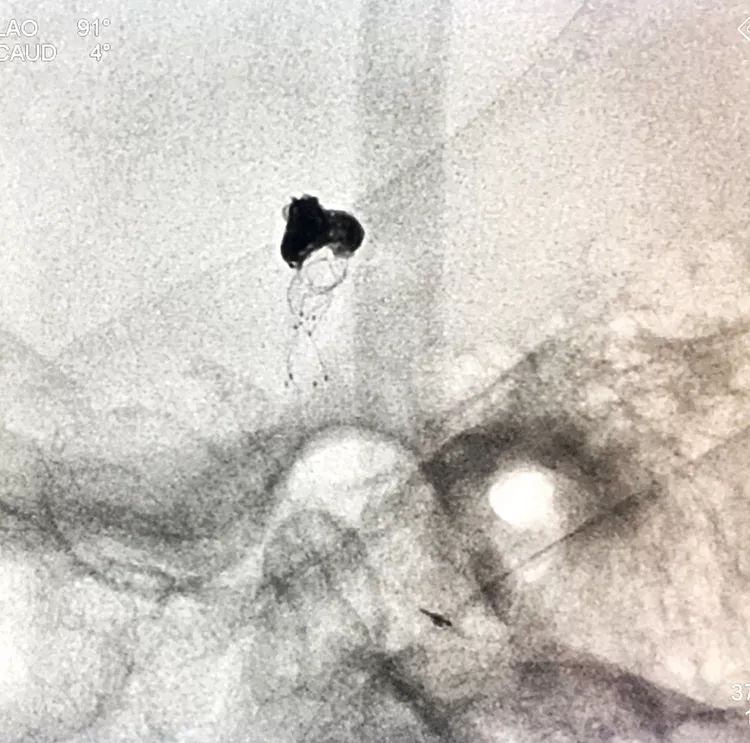

在支架保护下输送弹簧圈栓塞瘤腔

此时从工作位(右斜17°反汤9°)看弹簧圈分布致密,微导管头已被顶到瘤颈处

工作位造影看动脉瘤栓塞满意,子瘤已不显影,是不是可以收手了呢?

旋转增强器透视观察各个投照角度弹簧圈的分布情况,侧位透视发现瘤腔后部的弹簧圈分布疏松,形成死腔,看来革命还未成功,同志尚需努力呀!

回头再观察左椎动脉造影的三维成像,发现瘤腔确实有向后方突出的分叶,明确弹簧圈团后部的空虚处仍是瘤腔的一部分

此刻微导管的管头被支架压在瘤腔前部,显然无法再深入到瘤腔后部的死腔,这根直头的微导管该结束使命了,

换用一根新的Echelon10微导管,头端塑成C型,以Arvigo14微导丝引导(先前的Sychro14微导丝的头端已经有损了),经LVIS支架内部接近瘤腔后部的死腔,但微导丝可以进入死腔,微导管头死活钻不进去,被LVIS支架的网丝挡住去路,怎么办?那就隔着渔网袜挠痒!